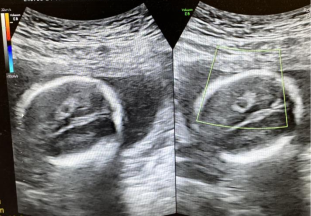

胎儿侧脑室宽度应<10 mm,当10㎜≤侧脑室宽度<15 mm时为轻度侧脑室增宽(可一侧或双侧)②。轻度侧脑室增宽与染色体异常、遗传综合征、脑发育异常、宫内感染(巨细胞病毒、弓形虫感染等)、颅内出血等相关。侧脑室宽度在10-12 mm的胎儿大部分预后良好,13㎜≤侧脑室宽度<15 mm的胎儿,其不良结局的风险增高。超声发现轻度侧脑室增宽,或侧脑室进行性增宽,需进行系统超声检查,排查胎儿的结构畸形, 胎儿非孤立性轻度侧脑室增宽时,建议行介入性产前诊断以及颅脑MRI,排除胎儿中枢神经系统异常可能。胎儿孤立性轻度侧脑室增宽时,建议定期产检并随访超声,动态观察,必要时行介入性产前诊断以及胎儿颅脑MRI。

见于1-3%正常胎儿,可单发,亦可多发,脉络丛囊肿与18-三体综合征相关。孤立性脉络丛囊肿预后良好,发现时,应进行非整倍体尤其是18-三体综合征的筛查③,低风险者常规产前随诊,高风险者仍需行介入性诊断。非孤立性脉络丛囊肿应行介入性诊断,排查胎儿染色体异常可能。